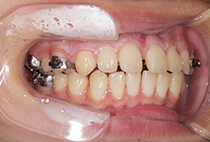

治療方法は、小さな上顎の成長誘導。

急速拡大装置と前方けん引装置を使用します。

かみ合わせもお顔立ちも大きく改善。

成長のピークに合わせて上顎をもう一度拡大し、前歯のかみ合わせをさらに安定化。

成長期の波に合わせることで、より調和の取れた横顔へ。